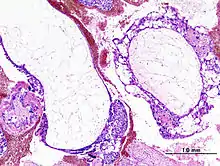

| Histopathologic image of hydatidiform mole (complete type). H&E stain. | |

A hydatidiform mole is a pregnancy/conceptus in which the placenta contains grapelike vesicles (small sacs) that are usually visible to the naked eye. The vesicles arise by distention of the chorionic villi by fluid. When inspected under the microscope, hyperplasia of the trophoblastic tissue is noted. If left untreated, a hydatidiform mole will almost always end as a spontaneous abortion (miscarriage).

Based on morphology, hydatidiform moles can be divided into two types: in complete moles, all the chorionic villi are vesicular, and no sign of embryonic or fetal development is present. In partial moles some villi are vesicular, whereas others appear more normal, and embryonic/fetal development may be seen but the fetus is always malformed and is never viable.

The diagnosis is strongly suggested by ultrasound (sonogram), but definitive diagnosis requires histopathological examination. On ultrasound, the mole resembles a bunch of grapes ("cluster of grapes" or "honeycombed uterus" or "snow-storm").[14] There is increased trophoblast proliferation and enlarging of the chorionic villi, and angiogenesis in the trophoblasts is impaired.[15]